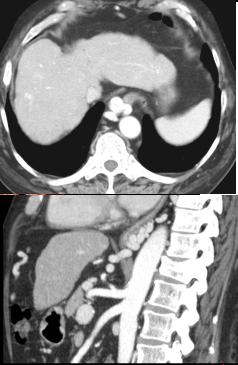

Image TOGD une hernie

hiatale de type III . Estomac en ce cas en roulement

dans le thorax et le cardia glisse au dessus

diapragmatique |

Meme cas

en coupe TDM sagitale |